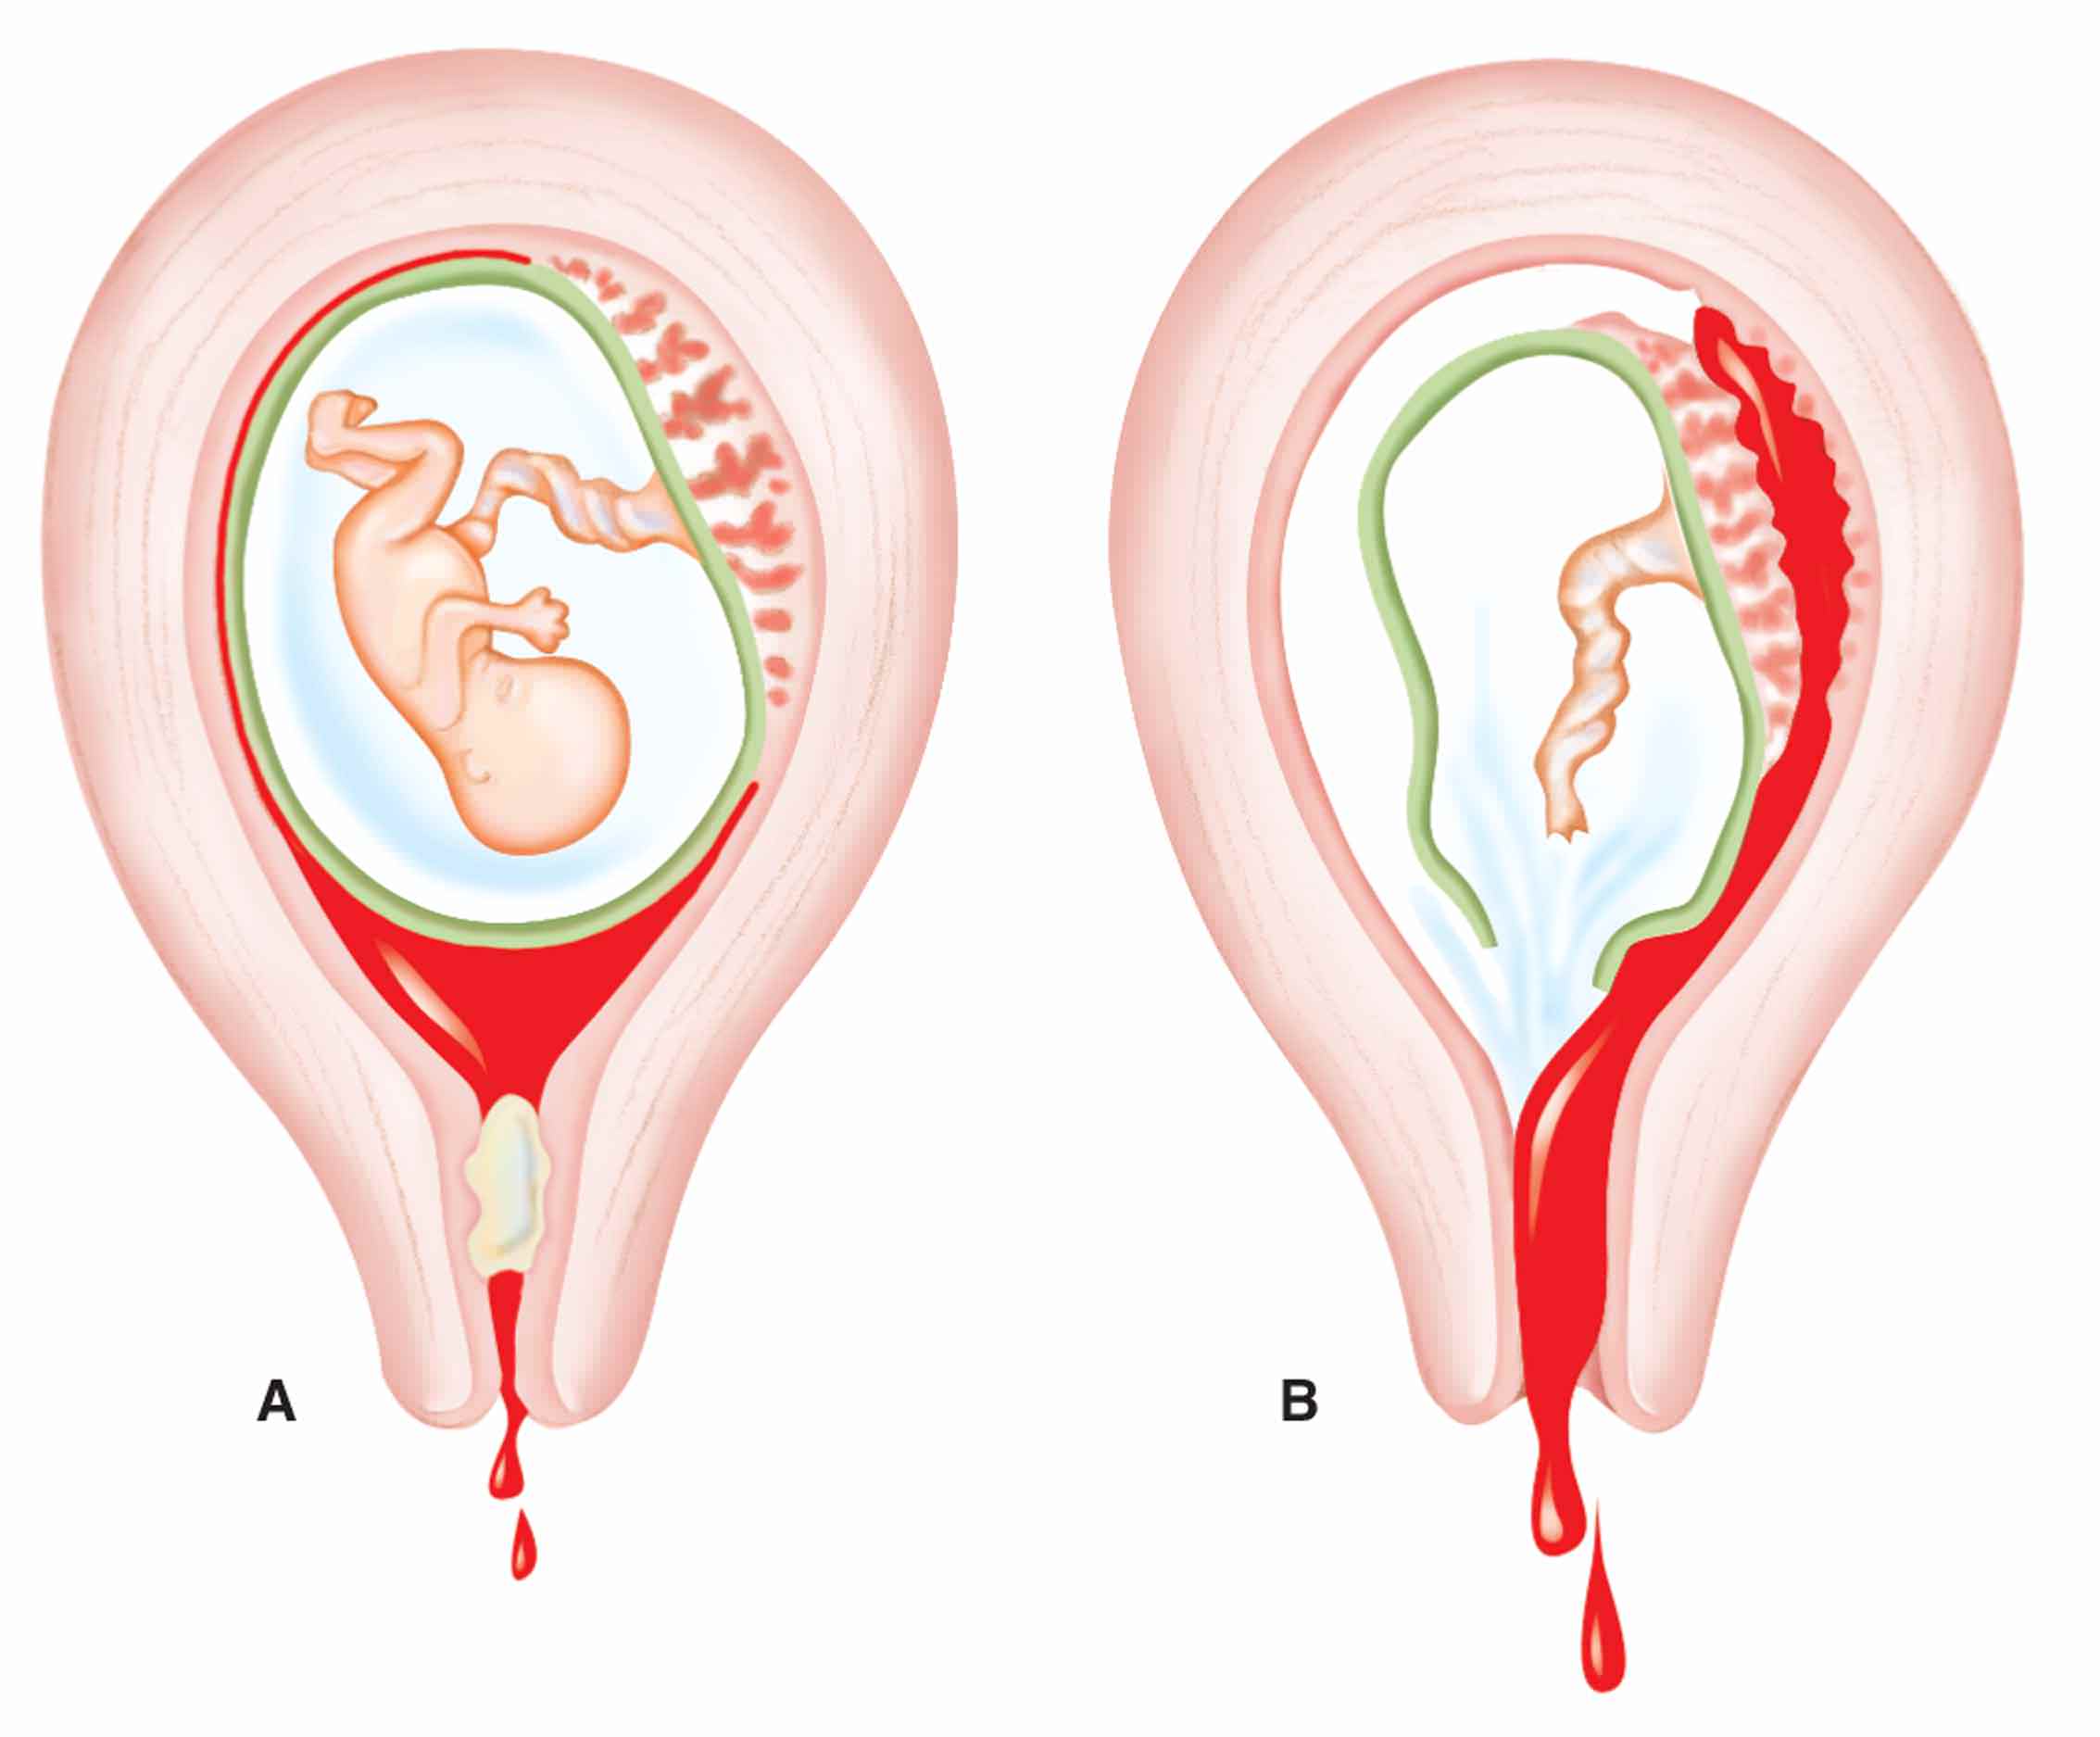

Околоплодный пузырь и плацента: структура и функции